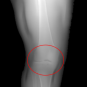

To obtain knee radiographs, we selected 55 leg CT volumes from the public SICAS medical image repository [18]. Each CT volume was simulated over with an angular increment of and projected onto the detector of the size using CONRAD [19], resulting in 60 DRRs per volume. All projections were normalized to the range of [0,1].

In addition, two different segmentations for each DRR were automatically generated as follows. The first segmentation extracted the leg contour using a threshold of 0.1, having a value of 0.5 for the contour and 0 for the background (refer to a(0)-c(0) in Fig. 3). The second segmentation extracted bones by thresholding the original CT volume, followed by forward projecting the bone. The bone projection was set to 0.5, and adding it to the contour segmentation resulted in the second segmentation, with bones having a value of 1 and contour a value of 0.5 (refer to d(0)-f(0) in Fig. 3). In total, 3300 radiographs are generated for each type of segmentation. They were randomly split into a 9:1:1 ratio for training, validation, and testing.

In this section, we provide qualitative and quantitative results of the two proposed diffusion-based methods and compare them with the baseline U-Net model. The first column of Fig. 3 showcases six randomly selected conditions: (a0)-(c0) show contour segmentations, and (d0)-(f0) denote segmentations containing contour and bones. In Fig. 3 (a1)-(f1), the images generated by U-Net contain blurred fine details in locations where bones overlap, despite maintaining the given shape, as highlighted by the red circle. In contrast, the results from CSM appear more realistic than the U-Net. However, their quality decreases with introduced constraints, as indicated by the red arrow in Fig. 3 (d2) and (f2). The results from CTM not only achieve nearly the same level of fineness as the labels but also provide reasonable results with respect to the given conditions as illustrated in the fourth column.